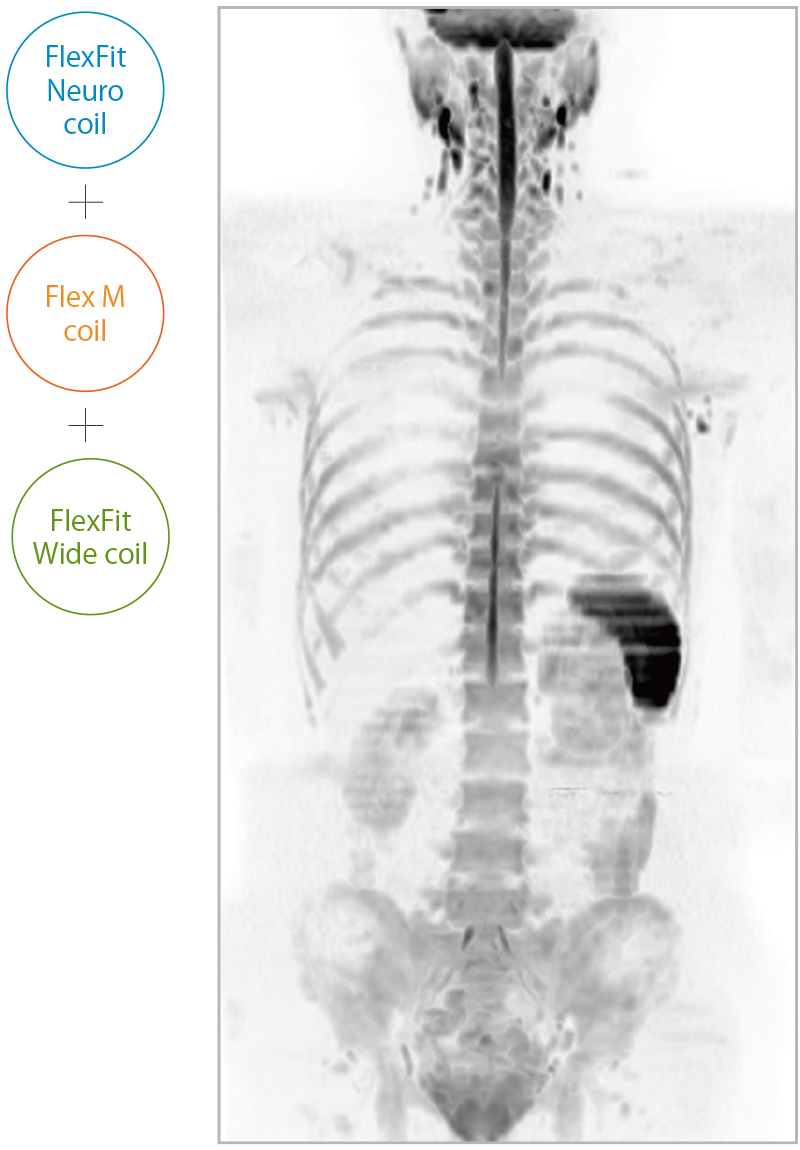

IP-RAPID×DLR PlusはVolumeScanやRadialScan、HalfScanといった基本撮像に加え、MultiContrastScanのFatSepやDWIなど多くの撮像法でお使いいただけます。広範囲DWIやWhole Spine撮像など時間のかかるWide Scanにも併用でき、多くの部位で従来よりも詳細な情報を得ることができます。

ECHELON Synergy ZeroHeliumはスライド装着でOneアクションセッティング可能なフレキシブル頭頸部用コイルや、撮りたい場所をフレキシブルにワイドにカバーできるFlexコイルを備え、部位に応じて柔軟に対応できます。